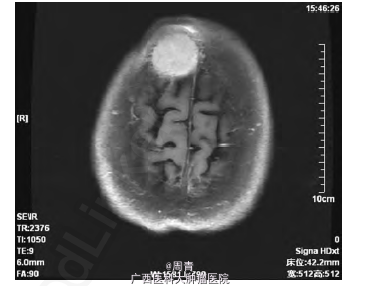

入院行体格检查发现: 右侧前额部包块,隆起明显,直径约5cm,形态规则,表面光滑,质软,边界清,无触痛,活动度差,周围可触及动脉搏动。患者未诉有任何疼痛、瘙痒等不适,追问病史,诉3 个月前偶然发现该肿物,生长缓慢。右侧前额部包块超声检查结果见: 皮下软组织内可探及范围约2.8cm×2.2cm×3.2cm的低回声包块,侵犯颅骨,形态尚规则,边界尚清,内回声尚均匀,可及动静脉血流信号,可引出动脉频谱,RI:0.90。考虑恶性肿瘤转移可能。头颅MRI 增强扫描,提示: 右额骨区可见35mm×35mm×37mm 大小占位病变,病变破坏颅骨内外板并膨胀性改变,增强扫描明显强化; 余颅内未见明确异常信号,脑室系统及脑沟、脑裂增宽; 中线结构无移位,符合恶性肿瘤改变( 图1) 。